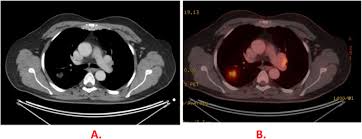

Pet Ct And Pet Mri In Ophthalmic Oncology Review from www.spandidos-publications.com Understanding the nature of cancer. Pet scans also prevent unnecessary surgeries and help suggest which cancer therapies are likely to be most effective for specific tumor types. Because of this high level of chemical activity, cancer cells the combined use of pet scans and ct scans is an effective method for detecting pelvic recurrences of rectal cancer. Pet scans use radioactively tagged molecules (or tracers) to image a wide array of molecular processes and when detected by a pet scanner, the tracers help your doctor to see how well your organs and tissues are working. A pet scan is particularly useful in detecting cancer because most cancers use more glucose than normal tissue uses. In this case, your body position will be very important. Cancer patients and their doctors now have access to a superior imaging technology in pet scans. A pet scan is most often used when other tests, such as mri scan or ct scan, do not provide enough information or physicians are looking for the potential spread of the breast cancer to lymph nodes or beyond.

Pet scans are very useful in detecting diseases like cancer because tumors will be a different color than surrounding tissue activity. Those are detected by pet scanner and a computer converts a signal into detailed images showing how organs are working. The tracer will collect in areas of. Possible risks of a pet scan. The pet scan detects the concentrated psma tracer, pinpointing these tumors for more effective treatment.

Those are detected by pet scanner and a computer converts a signal into detailed images showing how organs are working. Pet is speeding the detection of new drug weapons in the war on cancer. The tracer will collect in areas of. Positron emission tomography (pet) imaging or pet scan is a nuclear medicine imaging. Pet scans use radioactively tagged molecules (or tracers) to image a wide array of molecular processes and when detected by a pet scanner, the tracers help your doctor to see how well your organs and tissues are working. Pet scans are a type of test that create 3 dimensional (3d) pictures of the inside of your body. Pet scan is a special type of imaging test in which tracers are injected & are absorbed into organs of body and images are obtained. For cancer and disease detection, the most commonly used nuclear scan is an fdg pet scan. The pet scanner detects signals that are given off from the tracer. Pet/ct, which is a combination of positron emission tomography (pet) with computerized tomography (ct), is a powerful, essential tool for cancer detection and diagnosis. Diagnosis, cancer staging, treatment diagnosed with cancer and are undergoing active treatment, assess treatment response efficiency and perform cancer monitoring with pet/ct scan! A pet scan is not specific for cancer. With that being said, not all cancers can be detected by pet.